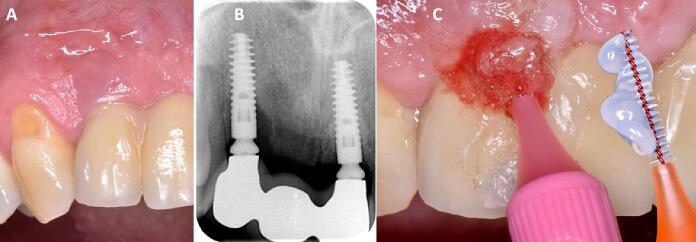

Globally, oral infections and inflammatory lesions persist as substantial public health concerns, necessitating the introduction of novel oral treatment protocols. Oral diseases are linked to various causative factors, with dental plaque/biofilm resulting from inadequate hygiene practices playing a predominant role. The strategic implementation of novel topical therapies holds promise for effectively controlling the biofilms, addressing oral infections and promoting enhanced oral wound healing. This review aims to providing a comprehensive overview of the available evidence pertaining to the potential efficacy of topical oxygen and lactoferrin-releasing biomaterials, exemplified by the blue®m formula, as novel oral care interventions within the scope of contemporary implantology, oral surgery and periodontology.

在全球范围内,口腔感染和炎性病变仍然是重大的公共卫生问题,因此需要引入新的口腔治疗方案。口腔疾病与多种致病因素相关,其中因卫生习惯不良导致的牙菌斑/生物膜起着主要作用。新型局部治疗方法的战略实施有望有效控制生物膜、解决口腔感染并促进口腔伤口愈合。本综述旨在全面概述有关局部用氧和释放乳铁蛋白的生物材料(以blue®m配方为例)作为当代种植牙学、口腔外科和牙周病学范围内新型口腔护理干预措施的潜在疗效的现有证据。